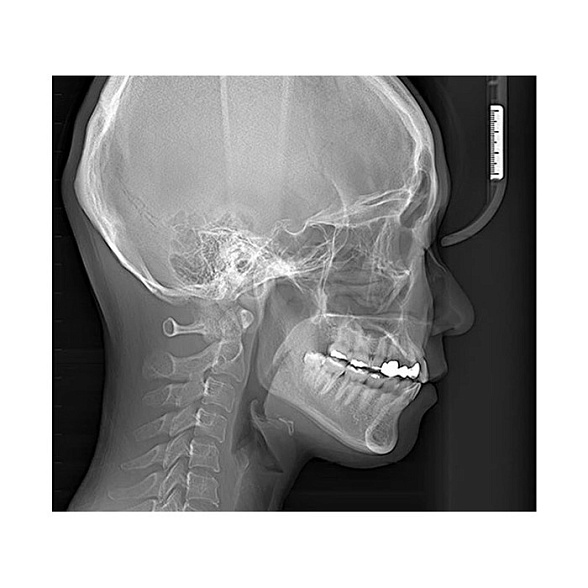

Veraview X800 P - комбинированная рентгеновская система высшего класса

Veraview X800 P: Комбинированная рентгеновская система для безупречной диагностики

Система Veraview X800 P представляет собой вершину технологий в области стоматологической визуализации. Это комбинированное решение, которое объединяет в себе возможности панорамной, цефалометрической и 3D-томографии, создавая универсальную диагностическую станцию высшего класса. Она разработана для клиник, которые стремятся предоставлять пациентам самый высокий уровень диагностики, планирования лечения и контроля его результатов.

Veraview X800 P — это не просто аппарат, это инвестиция в точность, эффективность и рост вашей клиники. Она позволяет проводить полный спектр рентгенологических исследований на одном устройстве, экономя пространство, время и бюджет, обеспечивая при этом бескомпромиссное качество изображений.

- Всесторонняя диагностика в одном аппарате: От панорамных снимков всей зубочелюстной системы до детальных 3D-томограмм отдельных сегментов и цефалометрического анализа для ортодонтии и ортогнатической хирургии. Больше нет необходимости направлять пациента в разные кабинеты или к сторонним специалистам.

- Высочайшее качество изображения: Цифровой плоскопанельный детектор с высоким разрешением обеспечивает исключительную четкость и детализацию. Это позволяет визуализировать мельчайшие анатомические структуры, ранние патологические изменения, точно оценивать состояние костной ткани, что критически важно для имплантации, эндодонтии и хирургии.

- Интеллектуальное управление дозой облучения (I-Dose): Система автоматически адаптирует параметры сканирования под анатомию каждого конкретного пациента и тип исследования. Это позволяет получать диагностически безупречные снимки при минимально возможной лучевой нагрузке, соблюдая принцип ALARA (As Low As Reasonably Achievable).

- Ортодонтия: Цефалометрический анализ для планирования лечения, оценка положения зубов и ретинированных клыков, контроль результатов.

Veraview X800 P — это комбинированная система. Помимо панорамных снимков, она позволяет делать цефалометрические снимки для ортодонтии и, что самое важное, получать объемные 3D-томограммы (КЛКТ). Это принципиально более высокий уровень диагностических возможностей.